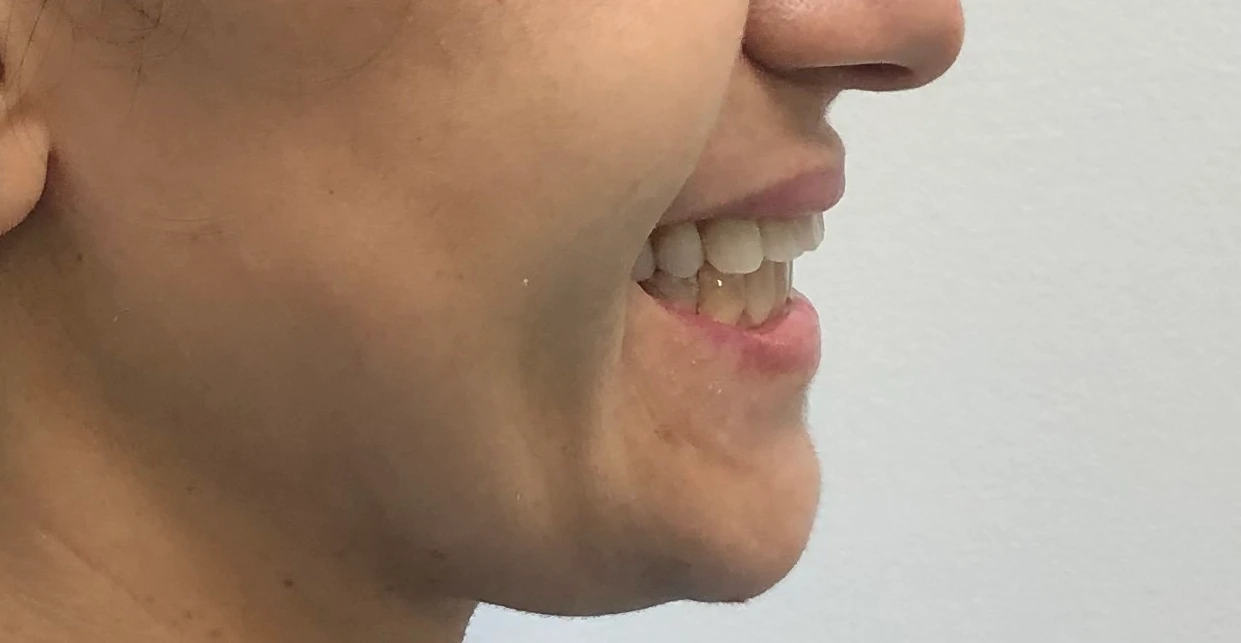

Caso de 8 meses

Caso de 1 ano e 6 meses

Caso de 6 meses

Caso de 4 meses

Caso de 10 meses

Caso de 8 meses

Caso de 1 ano e 5 meses

Caso de 1 ano e 2 meses